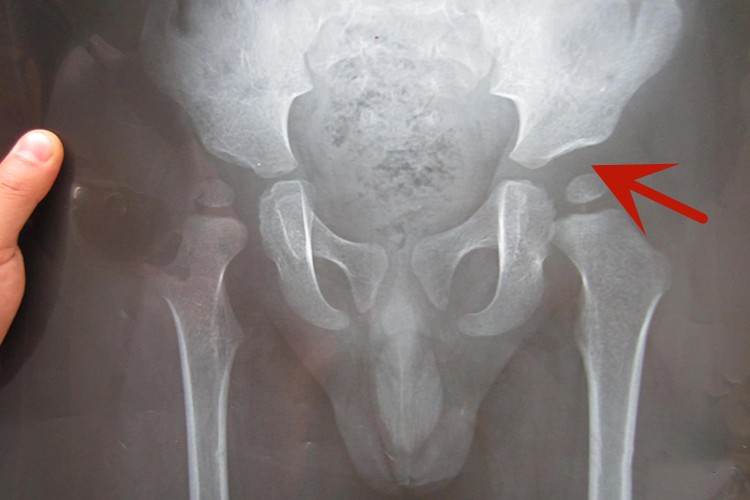

影像学X线可见股骨头向外上方脱位,髋臼发育差,X线下可测量髋白角、Shenton线、XX线和关节四分区。